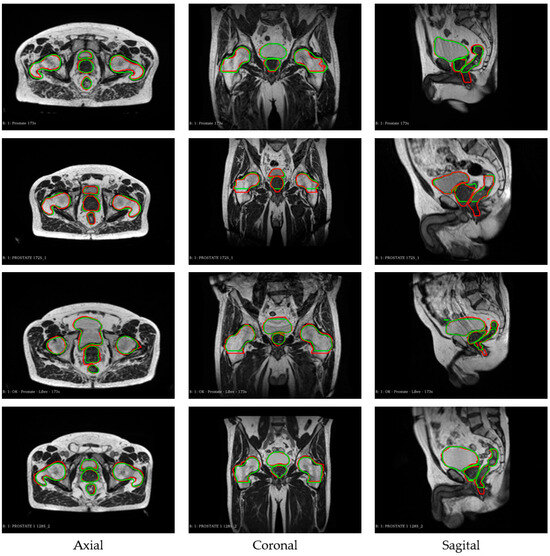

3. Results

| Organs | 2D | 2.5D | ||

| Dice ± STD | HD ± STD (mm) | Dice ± STD | HD ± STD (mm) | |

| Rectum | 0.84 ± 0.12 | 5.20 ± 4.86 | 0.84 ± 0.10 | 5.29 ± 5.04 |

| Bladder | 0.89 ± 0.12 | 9.73 ± 7.78 | 0.92 ± 0.09 | 6.13 ± 5.46 |

| Femoral head right | 0.87 ± 0.08 | 6.83 ± 6.26 | 0.88 ± 0.08 | 7.72 ± 5.27 |

| Femoral head left | 0.88 ± 0.08 | 6.64 ± 5.40 | 0.88 ± 0.08 | 7.02 ± 6.15 |

| Prostate | 0.79 ± 0.18 | 9.03 ± 8.40 | 0.80 ± 0.15 | 7.08 ± 5.81 |

| Overall Score | 0.85 ± 0.11 | 7.49 ± 6.54 | 0.87 ± 0.10 | 6.65 ± 5.33 |